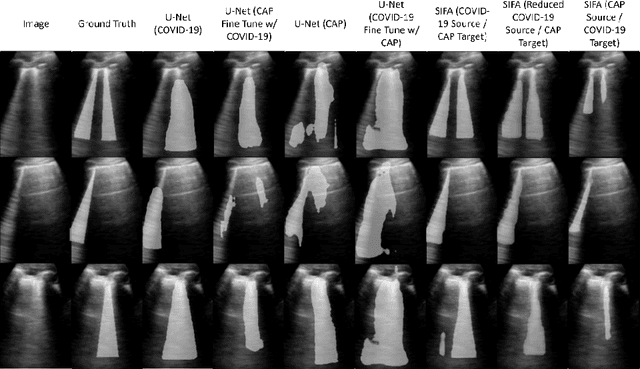

Abstract:Lung ultrasound imaging has been shown effective in detecting typical patterns for interstitial pneumonia, as a point-of-care tool for both patients with COVID-19 and other community-acquired pneumonia (CAP). In this work, we focus on the hyperechoic B-line segmentation task. Using deep neural networks, we automatically outline the regions that are indicative of pathology-sensitive artifacts and their associated sonographic patterns. With a real-world data-scarce scenario, we investigate approaches to utilize both COVID-19 and CAP lung ultrasound data to train the networks; comparing fine-tuning and unsupervised domain adaptation. Segmenting either type of lung condition at inference may support a range of clinical applications during evolving epidemic stages, but also demonstrates value in resource-constrained clinical scenarios. Adapting real clinical data acquired from COVID-19 patients to those from CAP patients significantly improved Dice scores from 0.60 to 0.87 (p < 0.001) and from 0.43 to 0.71 (p < 0.001), on independent COVID-19 and CAP test cases, respectively. It is of practical value that the improvement was demonstrated with only a small amount of data in both training and adaptation data sets, a common constraint for deploying machine learning models in clinical practice. Interestingly, we also report that the inverse adaptation, from labelled CAP data to unlabeled COVID-19 data, did not demonstrate an improvement when tested on either condition. Furthermore, we offer a possible explanation that correlates the segmentation performance to label consistency and data domain diversity in this point-of-care lung ultrasound application.